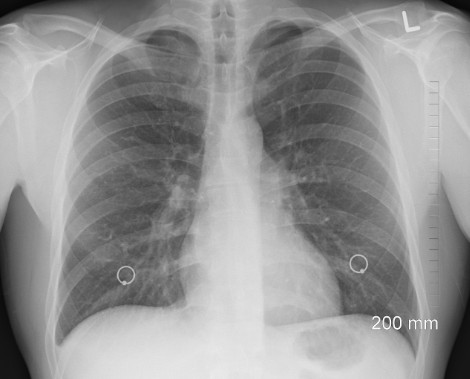

폐렴은 감염성 질환으로 폐 조직에 염증이 발생하는 질병입니다. 폐렴의 치료 절차는 감염의 원인과 심각성에 따라 다소 상이할 수 있지만, 일반적으로 다음과 같은 절차로 진행됩니다. 의료 전문가는 환자의 증상과 신체 검사, X-레이, 혈액검사, 기침 표본 검사 등을 통해 폐렴인지를 확인하고 감염의 원인을 파악합니다. 세균이 원인인 경우, 항생제를 투여하여 감염을 제거합니다. 항생제의 선택은 세균의 종류와 감수성 패턴, 환자의 연령, 건강 상태 등을 고려하여 결정됩니다. 바이러스가 원인인 경우에는 항바이러스 약물을 투여하여 바이러스의 증식을 억제합니다. 발열, 기침, 가래 등의 증상을 완화하기 위해 진통제, 해열제, 기침 억제제 등의 약물이 사용될 수 있습니다. 호흡이 어려운 경우나 산소 부족이 의심되는 경우, 산소 치료를 시행하여 호흡 기능을 개선합니다. 폐렴은 몸이 회복하기 위해 충분한 휴식이 필요합니다. 환자는 치료 기간 동안 적절한 휴식을 취해야 합니다. 감염으로 인해 탈수되는 것을 방지하기 위해 수액 치료를 시행합니다. 중증의 폐렴이나 취약한 군일 경우에는 입원하여 치료를 받는 것이 필요할 수 있습니다. 폐렴의 치료 절차는 환자의 상태와 감염의 원인에 따라 다를 수 있으며, 증상이 나타나면 즉시 의료 전문가와 상담하여 적절한 치료를 받는 것이 중요합니다. 특히 노인, 어린이, 만성 질환자 등은 폐렴에 더 취약하므로 예방을 위해 백신 접종과 규칙적인 예방접종을 권장합니다. 예방이 중요하며, 감염 예방을 위해 손 씻기, 마스크 착용, 건강한 식습관 등을 실천하는 것이 폐렴을 예방하는 데 도움이 됩니다.